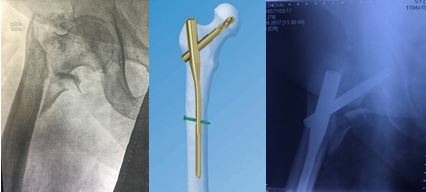

Переломы бедренной кости

Переломы бедренной кости часто сопровождаются массивной кровопотерей, что требует проведения оперативного вмешательства в кратчайшие сроки и с наименьшим повреждением мягких тканей. Отсутствие возможности передвигаться и вынужденный постельный режим чреваты развитием жизнеугрожающих осложнений со стороны органов дыхания, сердечно-сосудистой и пищеварительной систем.

Чаще всего встречаются переломы проксимального отдела бедренной кости: шейка бедра, вертельная области (чрезвертельные и подвертельные), диафизарные переломы и переломы дистального отдела бедренной кости. Больше всего им подвержены пожилые люди. Это связано с наличием остеопороза. В молодом возрасте эти переломы возникают вследствие высокоэнергетической травмы (падение, удар).

В ЦТиО ГВКГ им. Н.Н. Бурденко проводится огромный спектр оперативных вмешательств: от внутреннего остеосинтеза до эндопротезирования тазобедренного сустава. Специалисты центра травматологии и ортопедии способны решить данные проблемы путем применения высокотехнологичной малоинвазивной операции, продолжительностью не более 40 минут.

Доступ к больному участку производится через небольшие разрезы и под контролем рентгеновского аппарата. Методика интрамедуллярного малоинвазивного остеосинтеза позволяет избежать высокой кровопотери. Она также обеспечивает возможность ранней активизации больного, что очень важно у возрастных пациентов. Возраст самого пожилого пациента, прооперированного в ЦТиО ГВКГ им. Н.Н. Бурденко, составил 93 года.